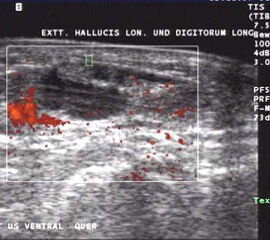

Sonographie

Die sonographische Untersuchung des Fußes wird in der Regel mit 7,5MHz durchgeführt. Erfasst und differenziert werden können ein Gelenkerguss bei Synovialitis, eine Bursitis bzw. eine Tenosynovialitis. Mit Hilfe des Power-Dopplers kann auch eine Aussage über die Krankheitsaktivität gemacht werden.

Flüssigkeit und erhöhte Gewebeperfusion im Powerdoppler sind Kennzeichen der rheumatoiden Arthritis im Ultraschall. Hier zeigt sich die Entzündung um die Extensor hallucis longus Sehne.